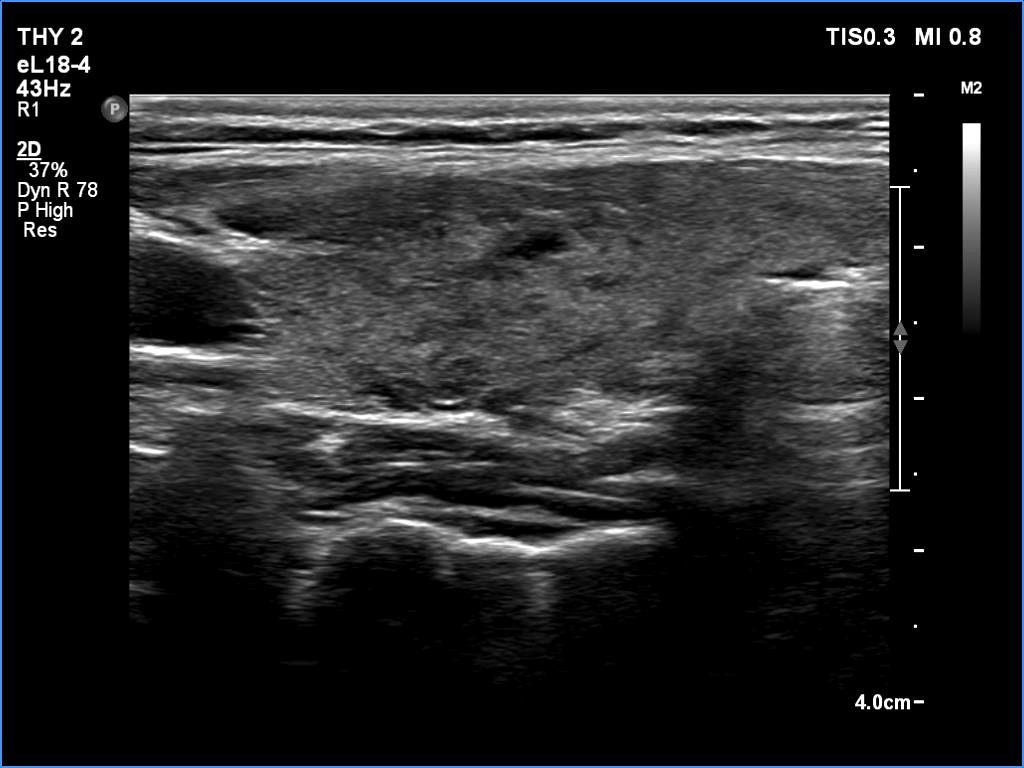

Second examination - five years later (second row of images)

Clinical presentation: The patient came to follow-up because she noticed a slow increase in the size of the left lobe.

Palpation: a firm nodule in the left lobe.

Laboratory tests: TSH 0.98 mIU/L.

The dimensions of the nodule in the left lobe were 40x25x43 mm, width, depth, length, respectively, the volume of the lesion was 22.5 mL.

Aspiration cytology resulted in follicular tumor. Surgery was advised.